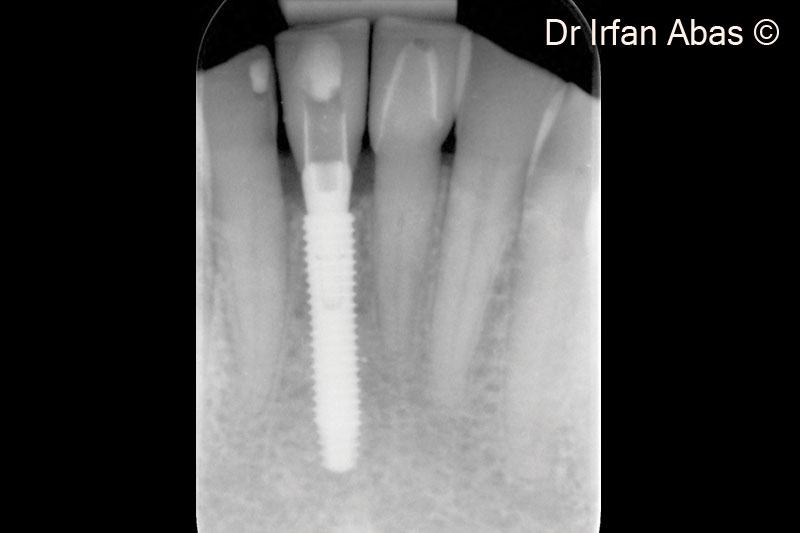

21. X-ray check after four months